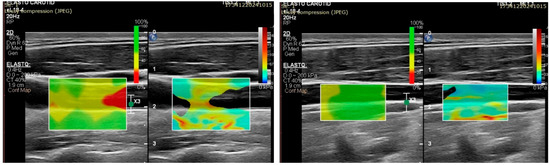

- A 2D color map of the shear wave velocities (SWVs) should be acquired, as it aids with the identification of homogeneous areas where the measurements are the most reliable. ROIs should be placed where the map shows a homogenous SWE distribution [56].